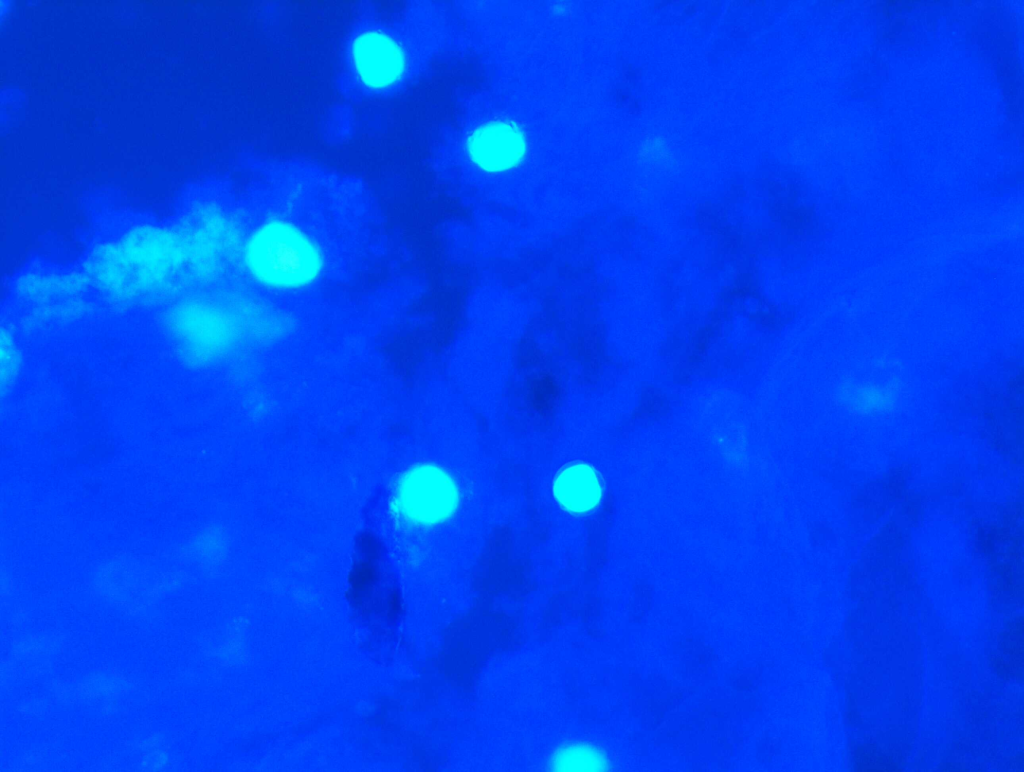

It is used to detect Acanthamoeba, a protozoan causing severe keratitis, especially in contact lens users.

PHMB (Polyhexamethylene Biguanide) is a polymeric biguanide antiseptic commonly used as a disinfectant in swimming pools and contact lens solutions. In ophthalmology, it is widely used as a topical 0.02% eye drop for treating Acanthamoeba keratitis.

PHMB disrupts microbial cell membranes by binding to phospholipids, leading to leakage of cytoplasmic contents and cell death. It is particularly effective against Acanthamoeba cysts and trophozoites, bacteria, and some fungi.

Chlorhexidine is a bisbiguanide antiseptic, used at 0.02% concentration as topical eye drops for Acanthamoeba keratitis and as an alternative to PHMB. It has broad-spectrum activity against Gram-positive, Gram-negative bacteria, and protozoa.